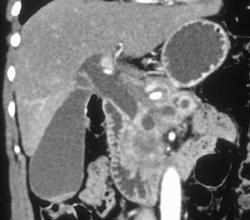

Pancreatic Cancer With Portal Vein Invasion